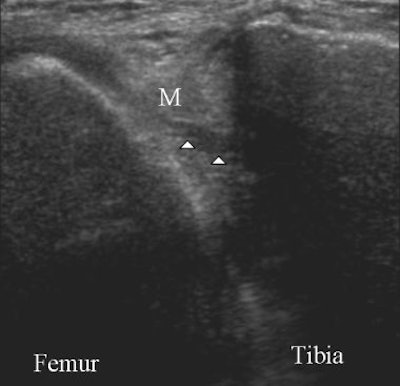

| Above, sagittal proton density-weighted MR image obtained through the posterior horn of the medial meniscus shows linear increased signal (arrow) extending to the inferior articular surface of the meniscus. Below, longitudinal ultrasonography obtained through the posterior horn of the medial meniscus shows a discrete hypoechoic cleft (arrowheads) extending to the tibial articular surface of the hyperechoic meniscus. Images courtesy of Dr. Gi-young Park. |